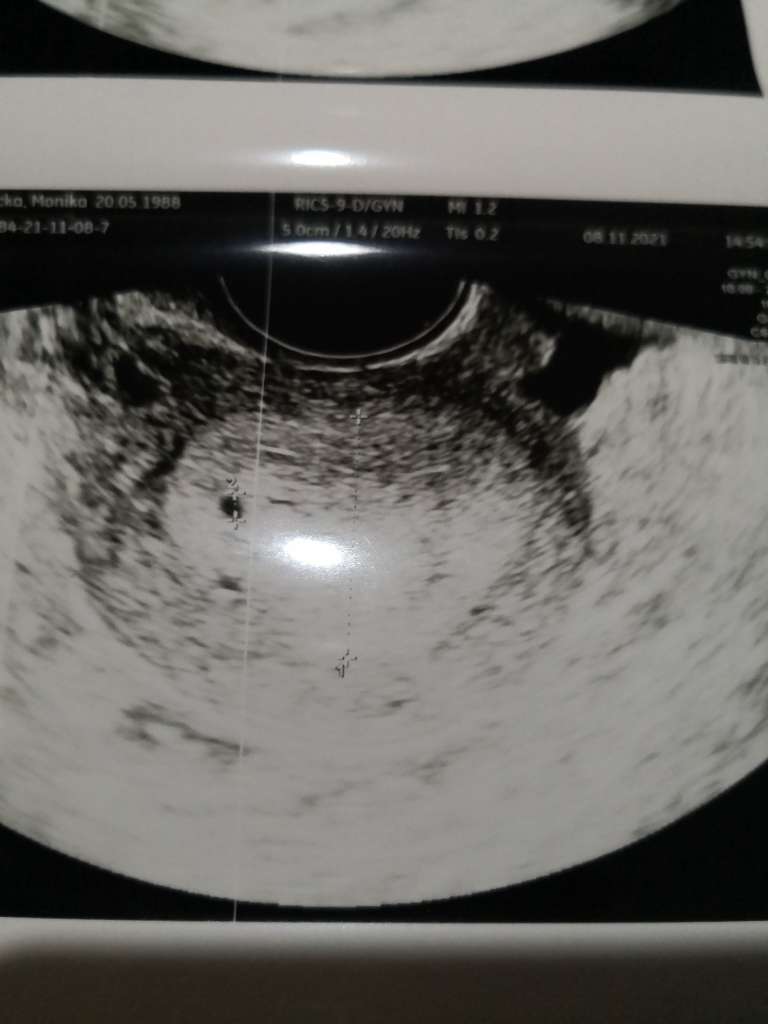

Myślałam, że wczoraj wstawiłam zdjęcie niezidentyfikowanego obiektu w mym ciele, ale widzę że nie, więc nadrabiam. Oglądajcie obcego

![]()

nie pomyślałam, na szybko strzelałam fotę, ale to tylko imię, nazwisko i data urodzeniaRzeczywiscie cos tam jest![]()